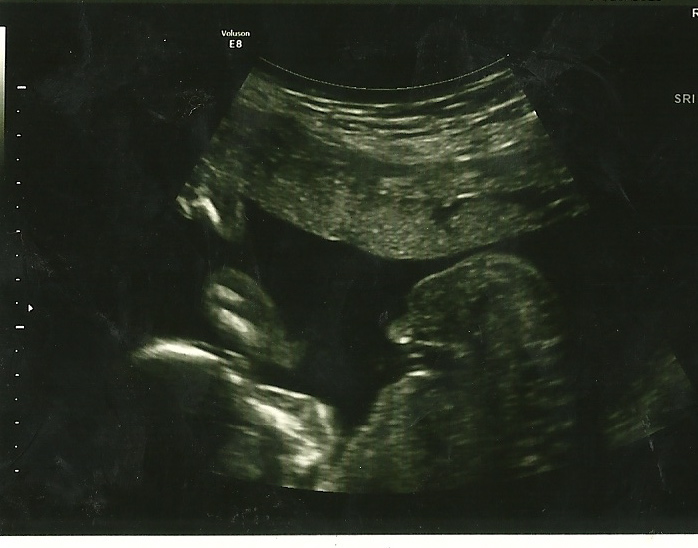

Slight boy lean x

Thank you for responding. I think top looks boy but the second pick has 3 lines which makes me think girl. Confusing. Again, thank you for your guess.

3 lines doesn't say anything on a side shot at 12 weeks. You need a potty shot at 15/16 weeks. Top one got me leaning boy but absolutely not sure!!

It's the blob on the top that makes it look boy BUT there is so much going on the blob area that I would not be surprised if it turned out a girl.

It's a boy!! Thanks for all your guesses and kind words. Now I am mama of 4 boys.

Attachment 12542 Was praying for a girl but got another beautiful boy.